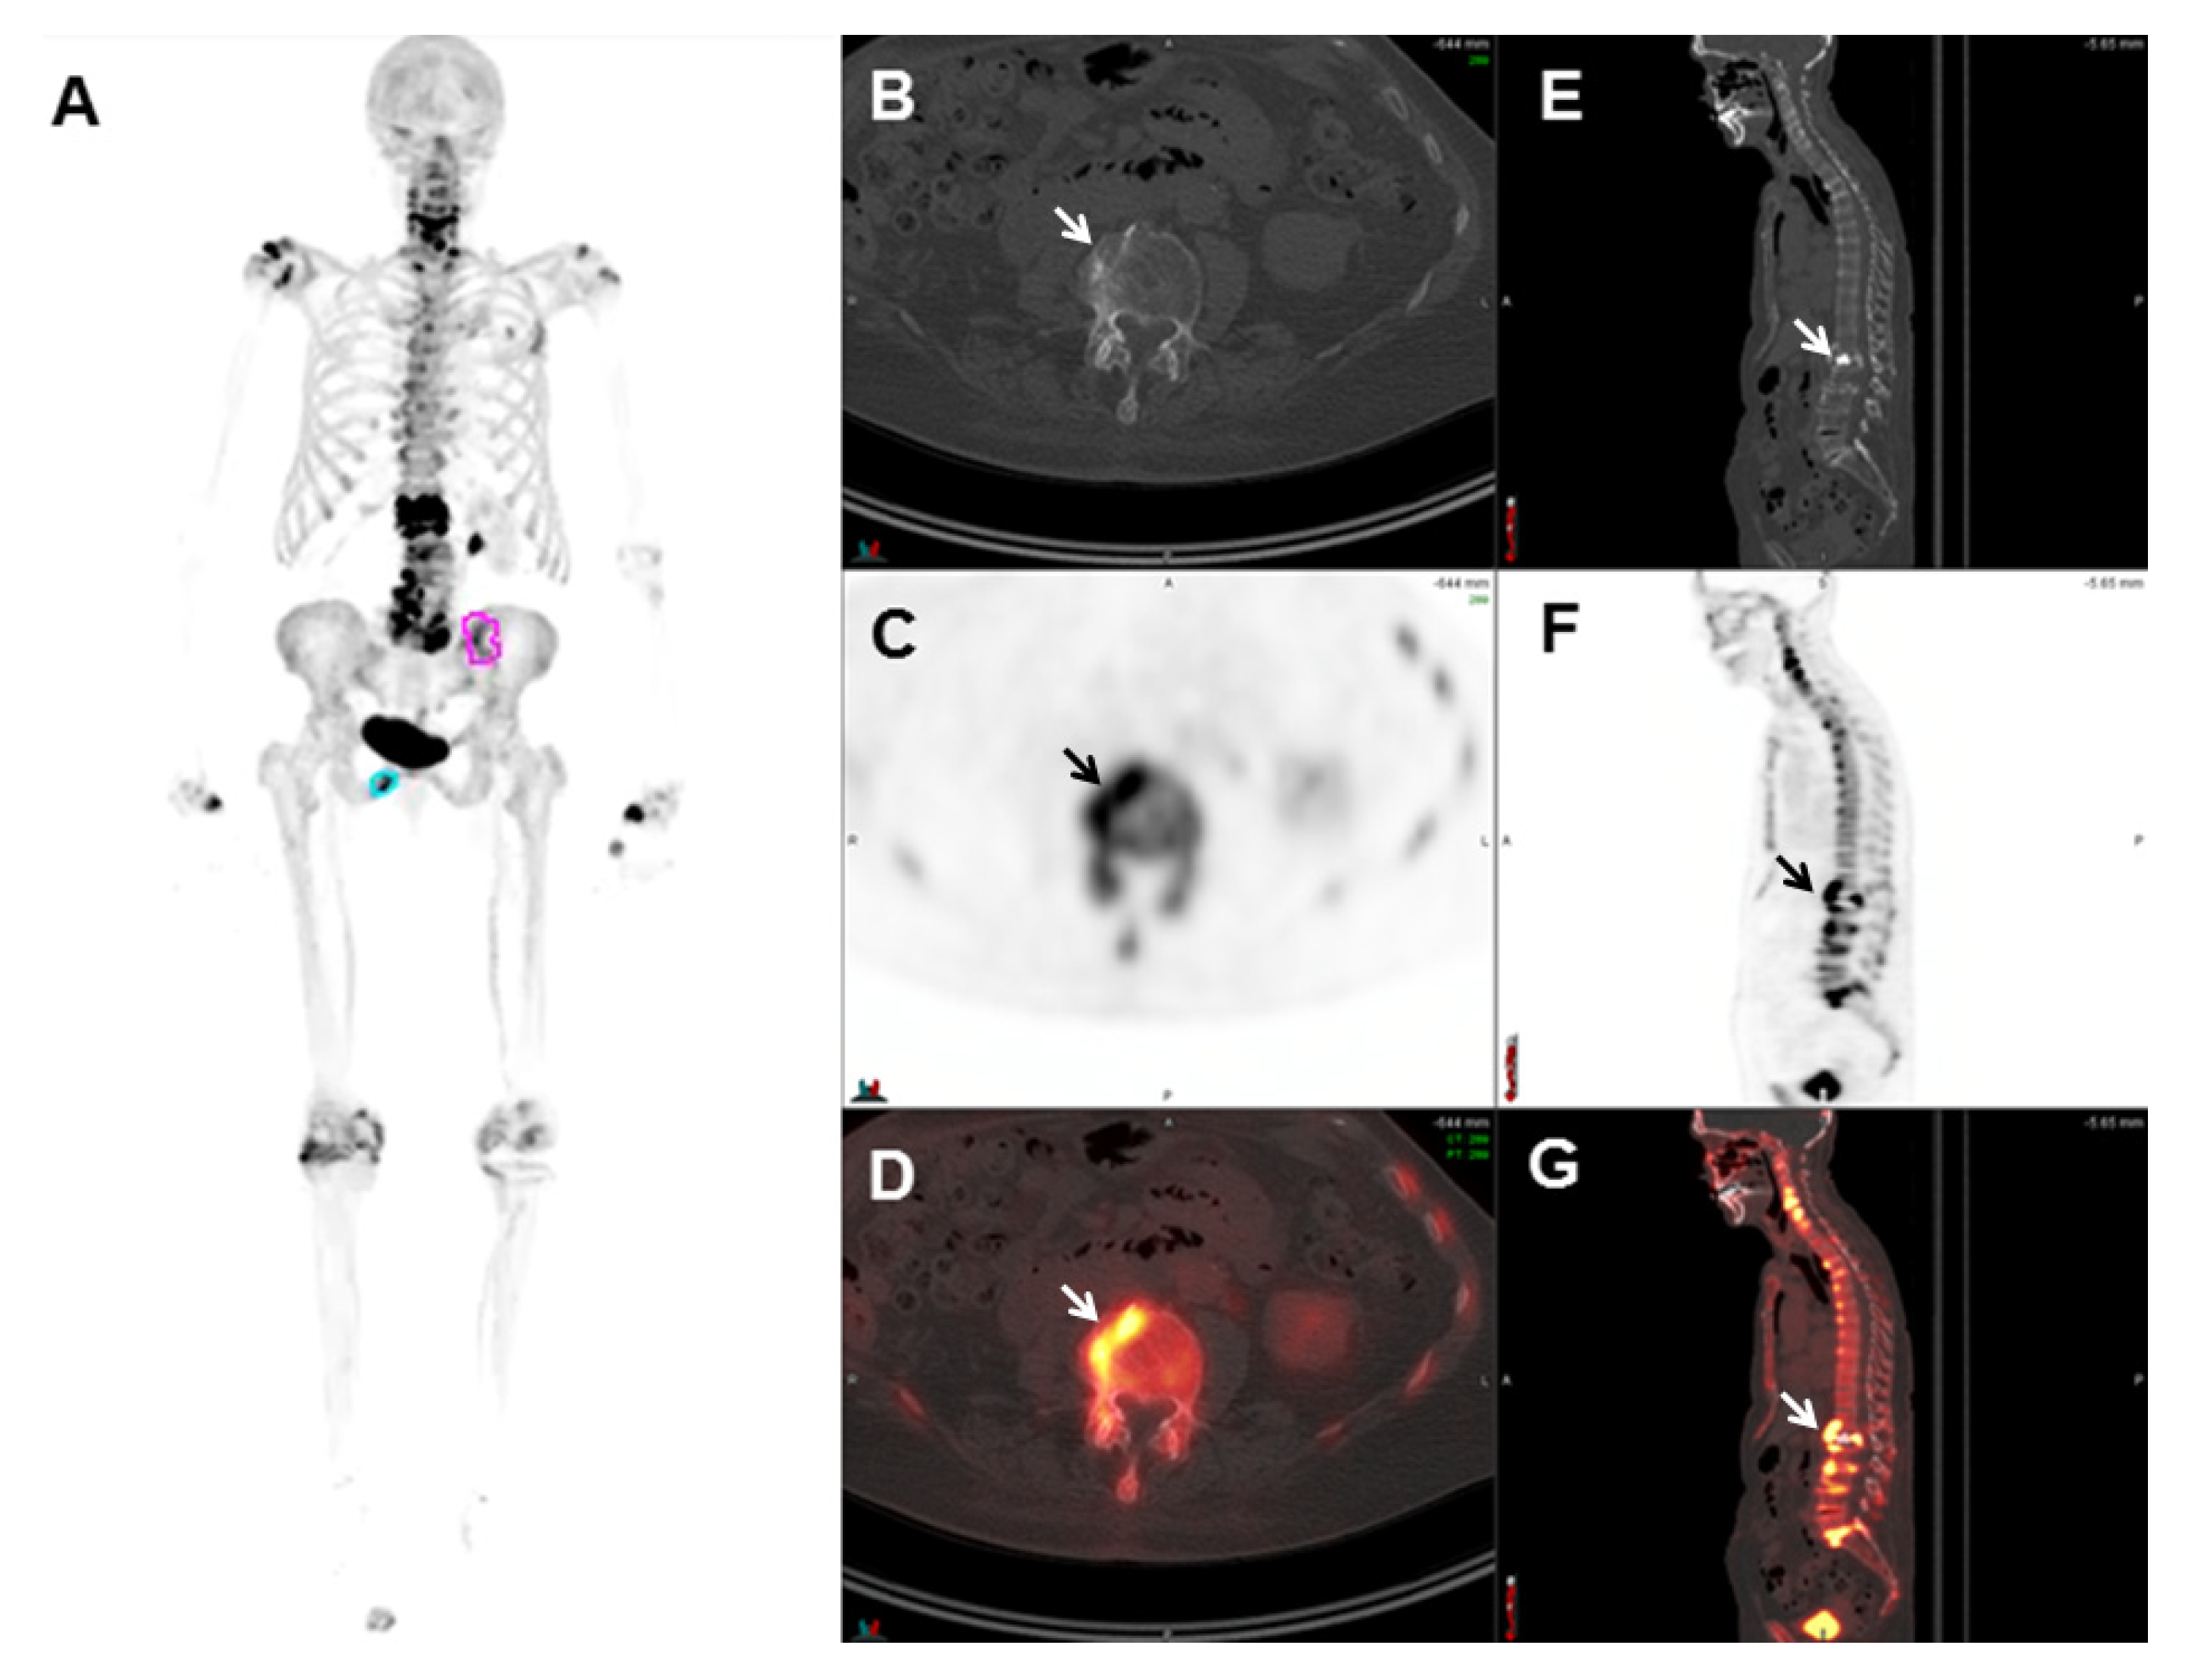

2.5.1. 68Ga-PSMA-11